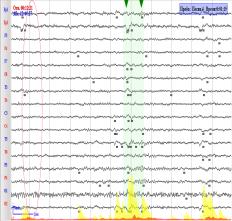

спектральной мощности ЭЭГ. Как пример рассмотрим паттерн аудиосигнала 5 - При

прослушивании отрезка аудио сигнала 5, на ЭЭГ фиксировали уменьшение амплитуды

бетта ритма электрического сигнала на 15%, на фоне роста основной частоты бетта-ритма на 20 % относительно таковых

средних характеристик фоновой записи

ЭЭГ . При влиянии музыкальной композиции «Parov

Stelar – Catgroove»

наблюдалось изменение зонального распределения бетта-ритма и распространению

его без выраженной ассиметрии по неокортексу человека. Для распределения бетта –ритма наблюдается

незначительная его асимметрия, которая составила 1,2% .(Рис.3).

Рис.3.

Пример записи ЭЭГ. Графическое представление записи электрических сигналов

мозга из всех отведений и зональное распределение бетта-ритма по неокортексу

человека. А. Паттерн фоновой

ЭЭГ. Б. Паттерн ЭЭГ на фоне аудио-стимула.